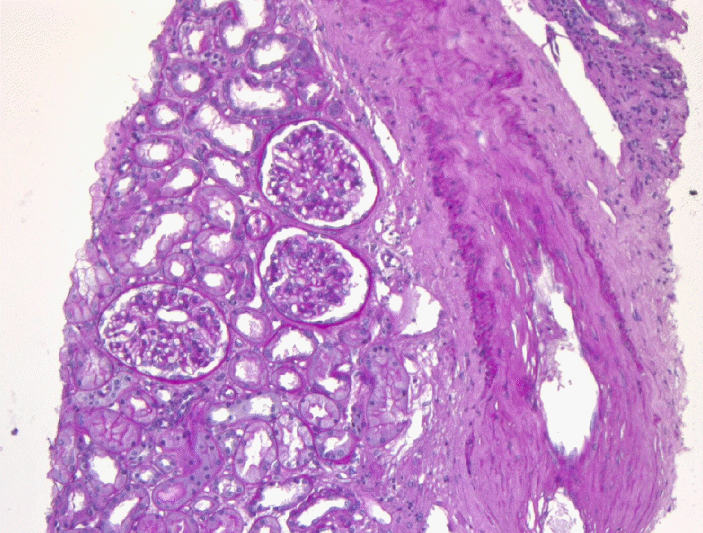

환 자: 69세, 여자주 소: 전신 부종현병력: 내원 1년 전부터 거품뇨가 발생하였으며 1개월 전부터 전신 무력감이 발생하였고 2주 전부터 체중증가 및 전신부종을 보여 내원하였다.과거력: 5년 전 고혈압을 진단받고 투약 중이었고 당뇨, 결핵, 간질환 등의 병력은 없었다.가족력: 특이사항은 없었다.신체검사 소견: 내원 당시 활력 징후는 혈압 160/90 mmHg, 맥박수 86회/분, 체온 36.5℃, 호흡수 20회/분이었다. 의식은 명료하였으며 만성 병색소견을 보였고 결막은 창백하였다. 흉부청진에서 심음 및 폐음은 정상이었다. 복부청진에서 장음은 정상이었고 간비장비대는 없었다. 전신에 부종 및 하지에 함요부종이 있었다.검사실 소견: 입원 당시 시행한 말초혈액 검사에서 백혈구 1,780/µL, 호중구 48.3%, 혈색소 9.2 g/dL, 적혈구용적율 26.1%, 혈소판 187,000/µL였다. 혈청 생화학 검사에서 총 단백 4.2 g/dL, 알부민 1.7 g/dL, AST 22 IU/L, ALT 16 IU/L, LDH 483 IU/L, BUN 19.9 mg/dL, creatinine 1.7 mg/dL, iron 56 µg/dL, total iron binding capacity 121 µg/dL, ferritin 208.9 ng/mL, 총 콜레스테롤 357 mg/dL, Na 132 mEq/L, K 2.9 mEq/L, Cl 98 mEq/L, C-reactive protein 0.37 mg/dL였다. 비타민 B12와 엽산 수치는 정상이었다. 소변검사에서 단백뇨가 4(+)였고 적혈구 10-20/HPF 검출되었으며 요당은 검출되지 않았다. 24시간 요 단백은 15,680 mg이었고, 소변 단백전기영동검사에서 모든 혈청 단백이 관찰되어 비선택적인 사구체성 단백뇨가 의심되었다.신장조직검사를 시행하였고 광학현미경 검사에서 13개의 사구체 중 3개의 사구체에서 전체 경화 소견을 보였으며, 전자현미경 검사에서 광범위한 발돌기의 융합(diffuse fusion of foot processes)을 보여(Fig. 1) 최소변화콩팥병증으로 진단하였다.골수검사를 시행한 결과 골수흡인도말 검사에서 거대핵세포의 수가 감소된 저세포성 골수가 관찰되었으며 세포충실도는 20-30%였고 myeloid:erythroid ratio는 14:1이었다. 유사분열, 핵파괴, 다핵 적혈모구와 같은 적혈구 형성이상은 드물게 관찰되었고 핵 모양의 비정상적인 변화와 세포질내 과립분포이상과 같은 과립구 형성이상은 흔히 관찰되었다(Fig. 2). 골수내 골수모세포는 18.7%로 모세포증가 불응빈혈-2로 진단하였다. 염색체 검사에서는 관찰된 20개의 분열세포 중 19개의 분열세포에서 t(11:19)(q23;p13.3)의 구조적 이상을 보였다(Fig. 3).최종적으로 이 환자는 최소변화콩팥병증을 동반한 골수형성이상증후군으로 진단할 수 있었고 international prognostic scoring system 점수는 2.5로 고위험군에 속하였다.치료 및 경과: 골수형성이상증후군의 치료는 신장기능부전으로 진단 후 바로 시작하지 못하였다. 신증후군의 치료로 이뇨제를 복용하던 중 호흡곤란, 하지 부종 증가 및 단백뇨 지속, 혈중 creatinine 수치 증가를 보여 진단 후 약 2개월경 혈액투석을 시작하였다. 투석을 시작하면서 프레드니솔론을 1 mg/kg 용량으로 복용하기 시작하였다. 프레드니솔론 복용 10일 후 백혈구는 1,050/µL에서 2,270/µL로 증가하였고 전신부종 및 단백뇨도 호전을 보였다. 3개월 후 백혈구 6,270/µL, 혈색소 10.8 g/dL, 혈소판 196,000/µL로 상당히 호전되었다.점차 경구 프레드니솔론을 감량하였고 복용 시작한지 5개월경 완전히 중단하였다. 중단할 당시 말초혈액은 백혈구 6,370/µL, 혈색소 11.1 g/dL, 혈소판 244,000/µL로 경한 빈혈외 특이소견이 없었다.1년 후 골수검사를 추적하였으며 골수흡인도말 검사에서 저세포성 골수가 관찰되었고 골수모세포는 1.9%, 세포분화는 정상적이었다(Fig. 4A and 4B). 염색체 검사에서 46,XX의 정상소견을 보였다. 말초혈액 혈구수 및 신장기능 또한 정상범위였다.프레드니솔론을 중단한지 3년 후, 전신 무력감 및 열감으로 내원하였고 말초혈액 검사에서 범혈구감소증을 보였다(백혈구 430/µL, 혈색소 6.8 g/dL, 혈소판 80,000/µL). 골수흡인도말검사에서 저세포성 골수로 형성이상소견이 다시 나타났고 골수모세포가 18%였다(Fig. 4C and 4D). 염색체는 정상이었다. 이에 골수형성이상증후군이 재발한 것으로 판단하였으나 신증후군과 관련된 소변검사 및 신기능은 정상범위에 있었다.골수형성이상증후군의 재발에 대해 아자시티딘(azacytidine) 치료를 시작하였다. 그러나 2차 치료 후 전격성 위막성 대장염(fulminant pseudomembranous colitis)으로 인한 패혈증으로 사망하였다.